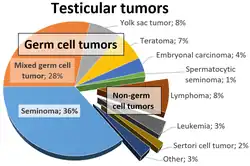

Risk factors include an undescended testis, family history of the disease, and previous history of testicular cancer.[5] More than 95% are germ cell tumors which are divided into seminomas and non-seminomas.[8] Other types include sex-cord stromal tumors and lymphomas.[4] Diagnosis is typically based on a physical exam, ultrasound, and blood tests.[2] Surgical removal of the testicle with examination under a microscope is then done to determine the type.[2]

Although testicular cancer can be derived from any cell type found in the testicles, more than 95% of testicular cancers are germ cell tumors (GCTs). Most of the remaining 5% are sex cord–gonadal stromal tumours derived from Leydig cells or Sertoli cells. A correct diagnosis is necessary to ensure the most effective and appropriate treatment. To some extent, this can be done via blood tests for tumor markers, but definitive diagnosis requires examination of the histology of a specimen by a pathologist. Testicular tumors are best classified by radical inguinal orchiectomy, which allows for histologic evaluation of the whole testicle and provides local tumor control.[39]

Most pathologists use the World Health Organization classification system for testicular tumors:[40]

Although testicular cancer is most common among men aged 15–40 years, it has three peaks: infancy through the age of four as teratomas and yolk sac tumors, ages 25–40 years as post-pubertal seminomas and non-seminomas, and from age 60 as spermatocytic tumors.[70]